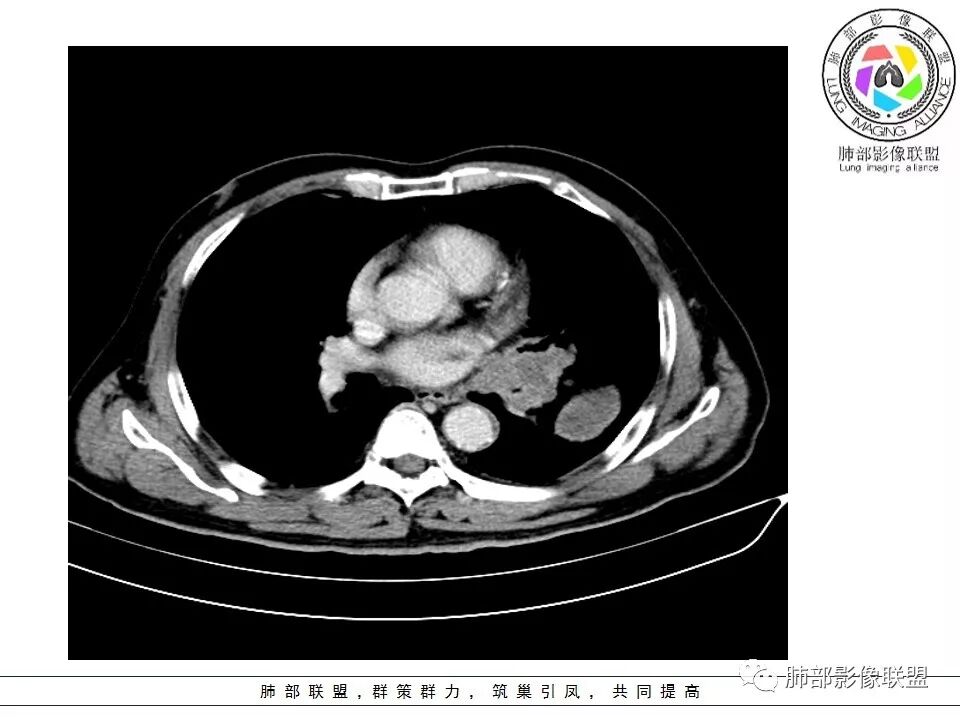

南边:病灶分为两大块,外围囊实性大肿块,支气管关系不密切,内带多发淋巴结,侵犯支气管、肺血管,恶性没问题,按理间叶为主,或不典型的癌,这不是一个中央型的肺癌,是外朝内进展的,奇怪的是边界这么清楚光滑,一般癌肉瘤、肉瘤类多,其次才是癌,远端也没有阻塞,大方向是这样,恶性,间叶来源?或者混合,恶性程度较高,鉴别就是结核,因为结核是妖

1.左肺下叶近肺门区肿块,肿块外围大,内带小,提示外围向中央生长,符合周围型SCLC沿支气管方向生长。

2.病灶边缘光滑,未见明显分叶、毛刺,符合神经内分泌癌、癌肉瘤及间叶来源肿瘤。

3.病灶内密度偏低,穿行血管未见明显异常,轻度不均匀强化,为乏血供病灶。病灶内可疑坏死区,未见空洞;乏血供符合SCLC,但坏死区不符合。

4.病灶区支气管以受压推移为主,管腔不规则,腔内通而不畅,提示病灶粘膜下为主,符合SCLC迁徙蔓延或间叶来源肿瘤。

5.病灶内有血管走行,血管局部受压,但是强化考虑为乏血供,提示病灶内肺动脉并不是供血血管,只是病灶侵袭性强把血管包埋而已,为血管包埋征;血流面光滑,血管包埋符合SCLC。

6.左肺门淋巴结肿大,与病灶局部融合分界不清,呈冰冻肺门;而纵隔内未见肿大淋巴结,冰冻肺门符合SCLC,但是病灶主体那么大,纵隔内没有明显肿大淋巴结,不是很符合SCLC娘小崽大的特点。

7.未见明显阻塞性炎症及阻塞性肺不张,更加提示病灶从外围向中央侵犯,符合SCLC罕见阻塞性肺不张。

病例小结

综上,影像学该病例符合肺内恶性,来源考虑神经内分泌癌、癌肉瘤或间叶来源肿瘤。老年男性,较大病灶伴有坏死,所以有群友考虑鳞癌、大细胞癌、癌肉瘤和肉瘤,但是鳞癌、癌肉瘤坏死常常合并空洞,而且像大细胞癌、癌肉瘤和肉瘤破坏力强,容易破坏血管;肉瘤一般不会引起肺门及纵隔的淋巴结肿大,所以肺门淋巴结肿大也不是很支持肉瘤。该病例部分征象支持小细胞癌(SCLC)的诊断。同病异影、异影同病都需要我们仔细甄别。